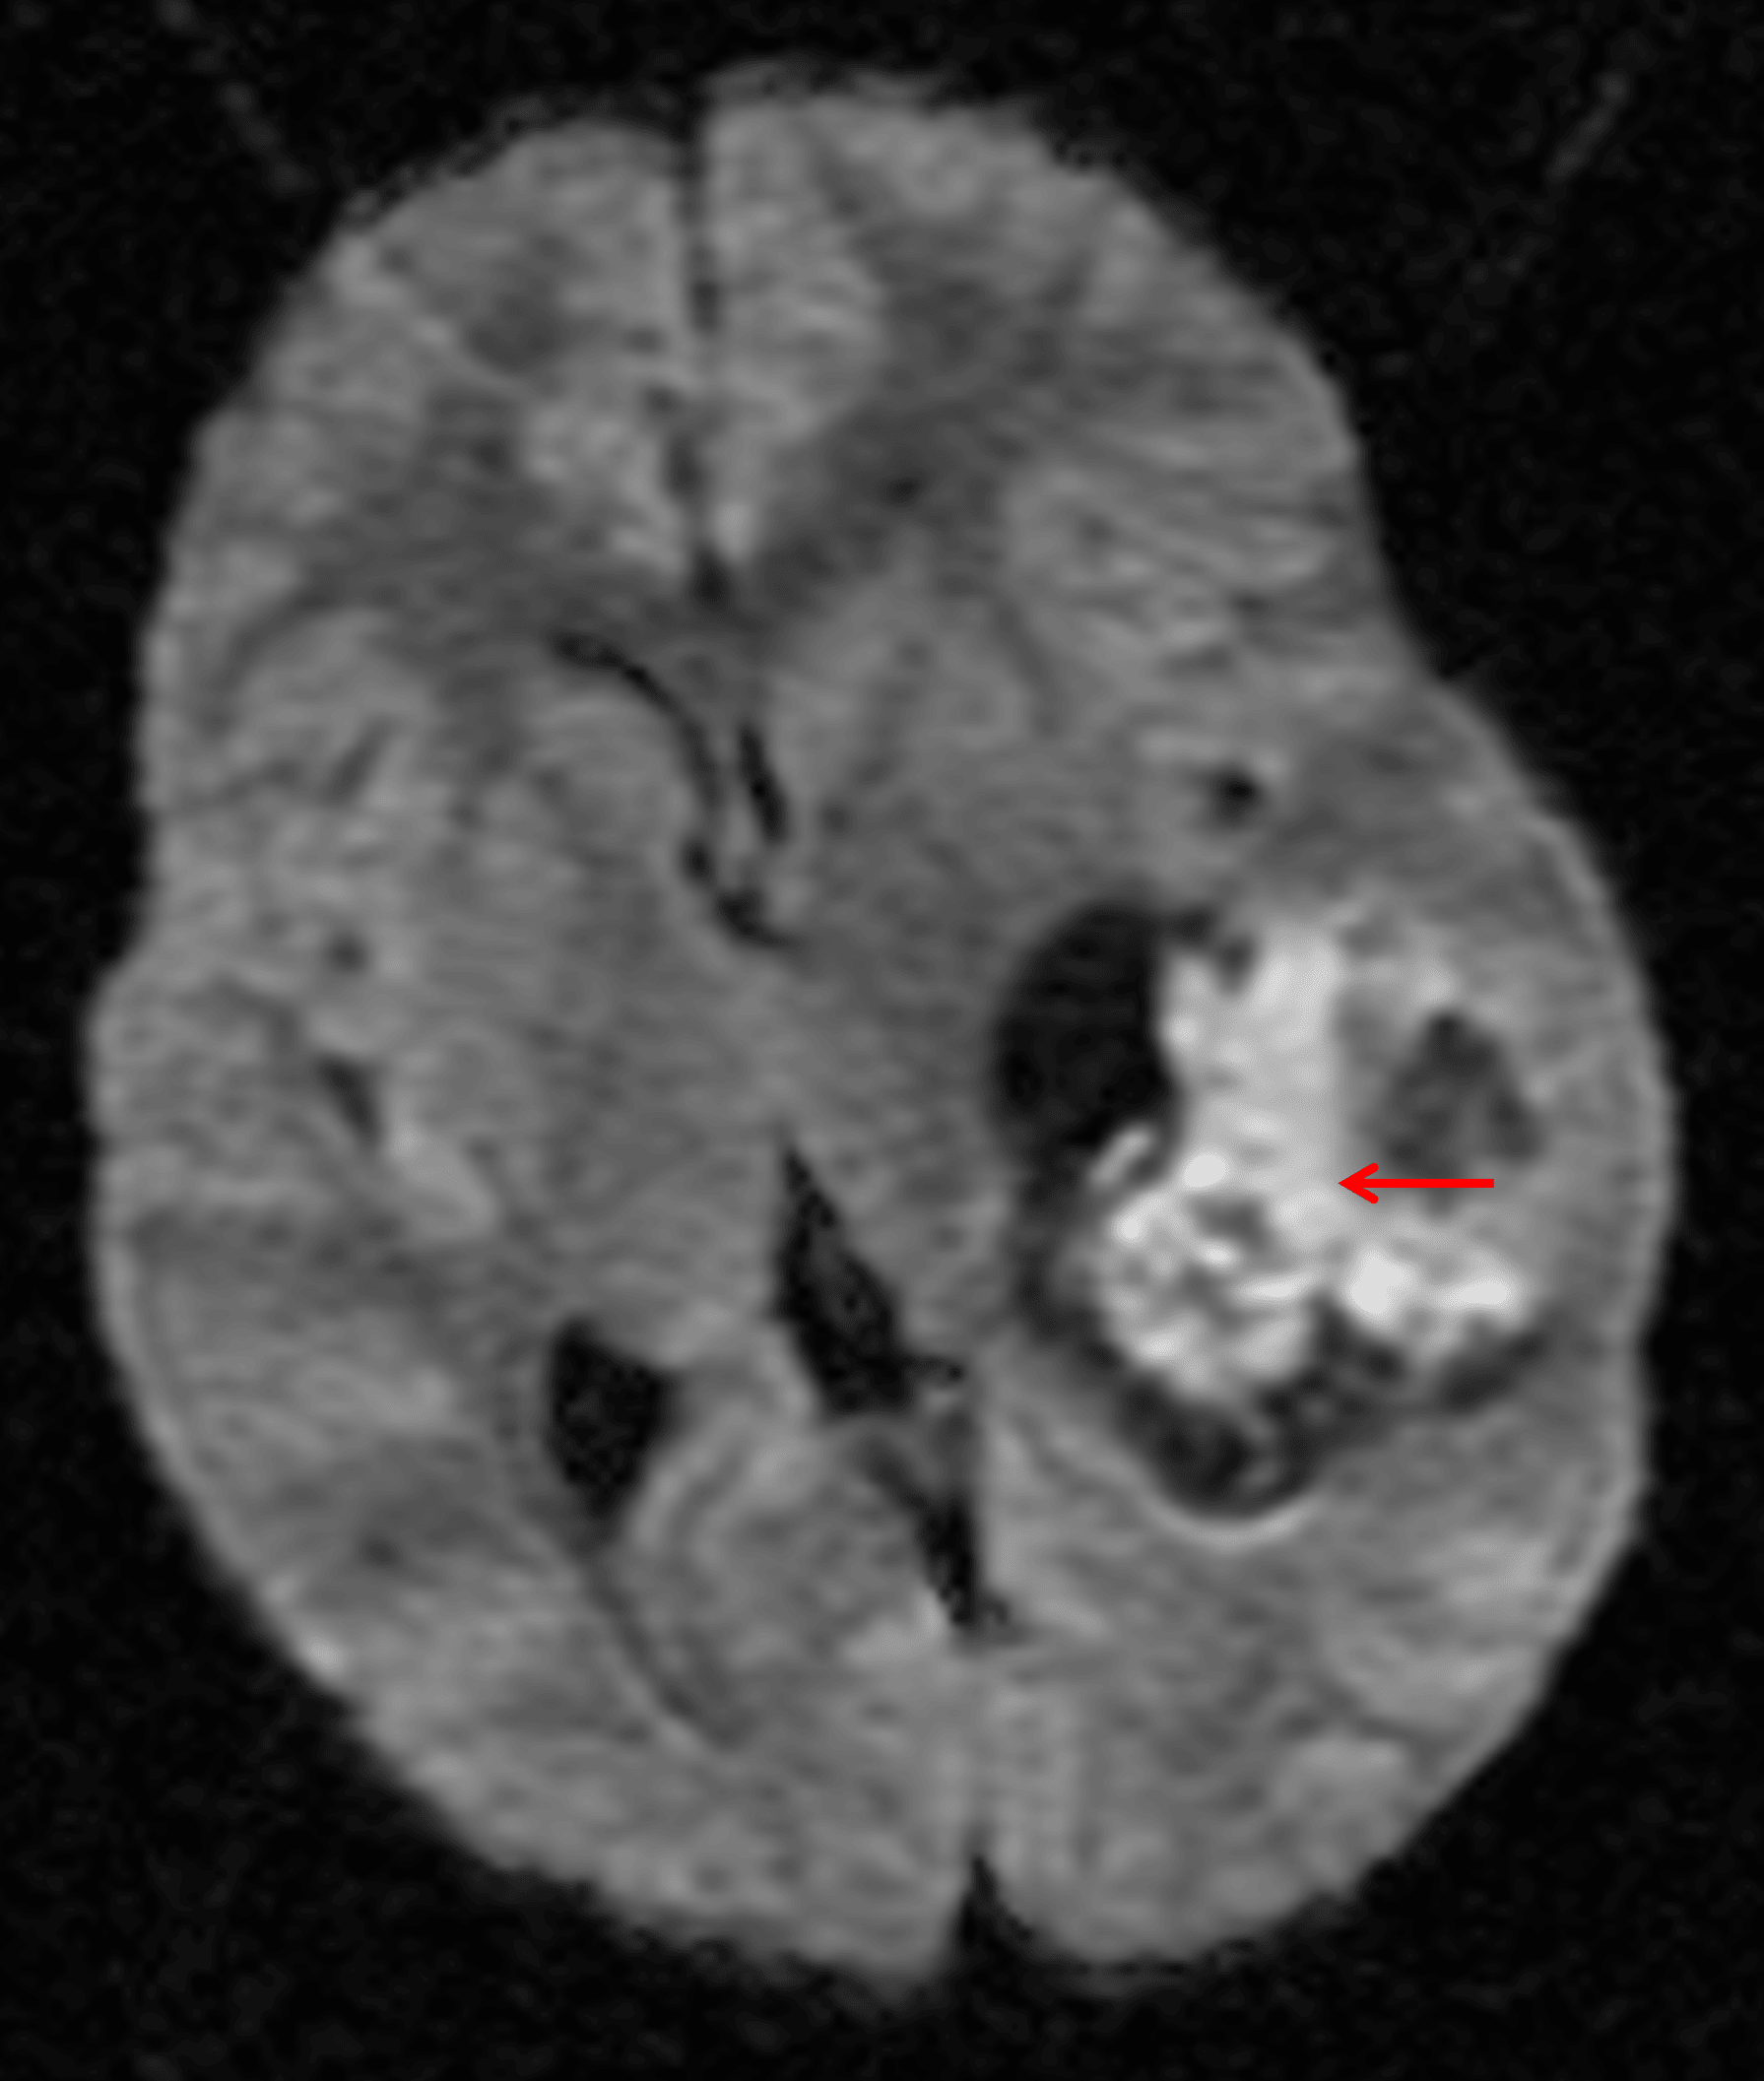

- Corresponding heterogeneous enhancement with matching areas of restricted diffusion

Areas of internal restricted diffusion (red arrow) corresponding with the enhancing components, indicative of hypercellularity.